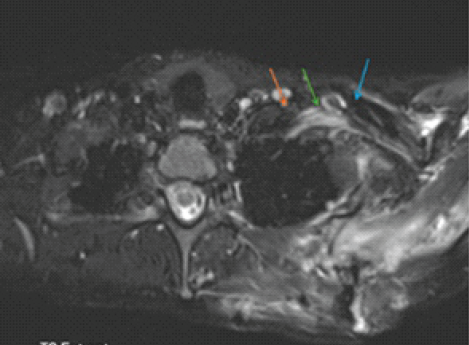

Dorsal Claviculectomy For Treatment Of Brachial Plexus Injury After Scapulothoracic Fusion: A Case Report And Literature Review

Huda S Saadeh , Yovag Morag , Ann Little , Yamaan S Saadeh

………………………………p.14-20